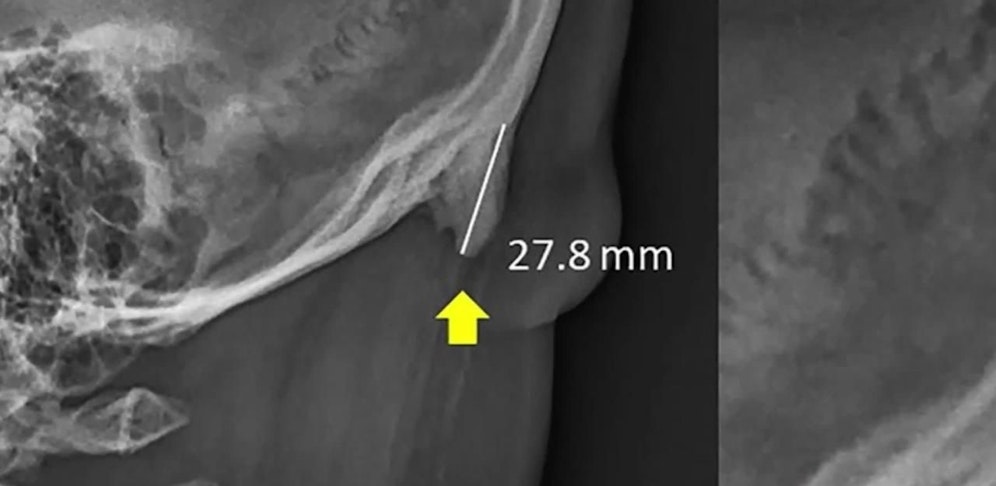

Konkret handelt es sich dabei um einen hornförmigen Vorsatz am Hinterkopf, genau über dem Nacken. Dieser ist mit den Fingern ganz leicht zu erfühlen und – eine Glatze vorausgesetzt – sogar für jeden sichtbar.

Dieses Knochenhorn galt bisher als sehr seltener Fund. Dass er so viele innerhalb der letzten Jahre gesehen hatte, machte Shahar stutzig. Gemeinsam mit einem Kollegen versuchte er das Rätsel zu lösen. Dazu analysierte das Duo rund 1.000 Röntgenbilder von Menschen im Alter von 18 bis 86 Jahren. Dabei notierten sie sich akribisch, welche Körperhaltung die Probanden mit dem zusätzlichen Horn einnahmen.